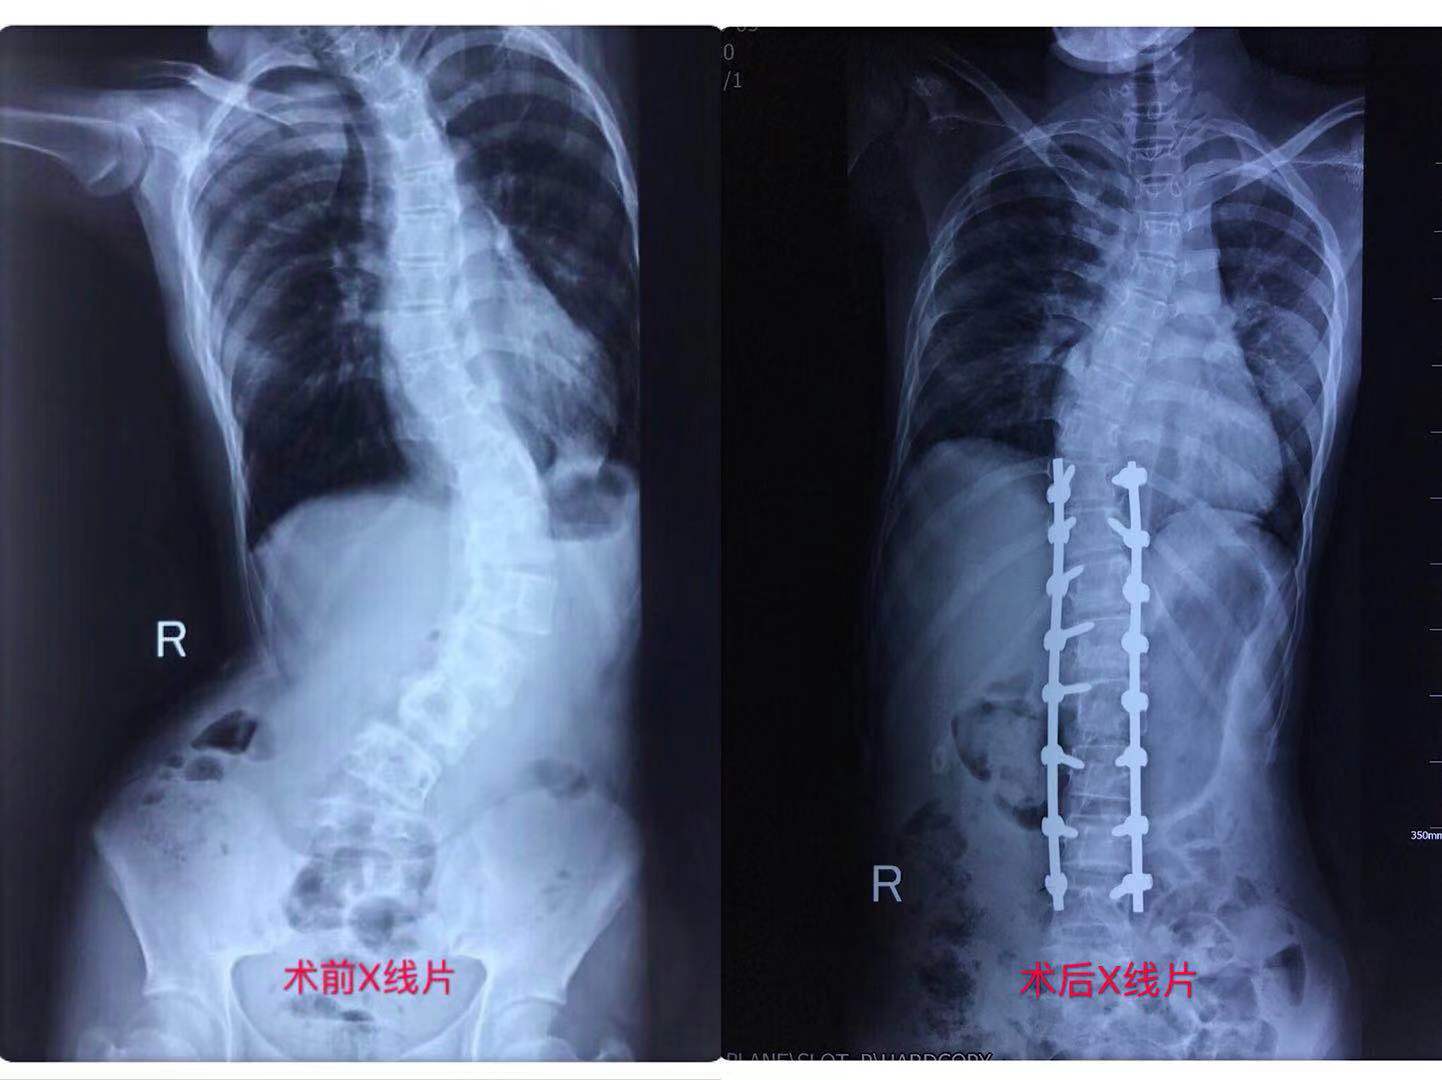

小阳(化名)原本是个开朗爱笑的女孩,因为患有严重的脊柱侧弯,在别人异样的眼光中她渐渐变得腼腆胆怯、沉默寡言。脊柱侧弯到底有多大的魔力,可以将一个人彻底改变?小阳的整个身形由于脊柱侧弯而出现异常形态,胸廓畸形、骨盆倾斜、长短腿……随着侧弯加重,更多的生理健康问题随之而来,神经受损、下肢麻木、呼吸障碍等。因为信息闭塞,小阳并不知道脊柱侧弯的危害有多大。轻者影响生活质量,重者可导致瘫痪,甚至危及生命!

在父母的陪同下,小阳来到兰大二院。见到康学文教授,在其专业的问诊及鼓励安抚下,她慢慢平复了那颗忐忑不安的心。而在初查之后,见到康教授团队认真讨论,研究制订手术方案时,她被瞬间燃起了希望和信心,露出久违的笑容。在专业团队的精心治疗下,短短数月,小阳原本寂静压抑的病房,渐渐有话语和笑声传出来。矫形手术的成功,不仅解除了小阳的身体疼痛,基本恢复形体外观。更令她欣喜的是,自己竟然神奇的长高了10厘米!出院当天,小阳洋溢着十几年来最灿烂的笑容,向医护人员一一道谢、告别,迈着自信坚定的步伐,走出医院,走向健康美好的明天。

对于脊柱侧弯患者,及时矫形治疗十分关键。因为,随着年龄的增长,侧弯加重将会带来更大的危害。兰大二院康学文教授团队实施这一帮扶项目,就是为了帮助经济困难的患者尽早得到治疗,从而舒展“被压缩”的身体,重新找回生活的信心和勇气。